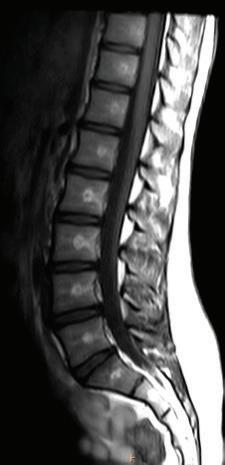

In T1 image sequences, fluid has low signal and appears dark on the image. Lipids and other specific tissues may have high signal and be bright (T1 hyperintensity). With contrast enhancement by a gadolinium-based contrast agent, tissue that contains the agent has high signal on T1-weighted images. In T2-weighted images, fluids (or tissue with high water content) have a high signal and appear bright (T2 hyperintensity) (Fig. 1-22 and Table 1.2). PD (proton density) sequences are neither T1 nor T2 weighted.

FIGURE 1-22 T1-weighted and T2-weighted axial MR lumbar spine images. Note that the cerebrospinal fluid (CSF) is hyperintense (bright) in T2 image and hypointense (dark) in T1 image.